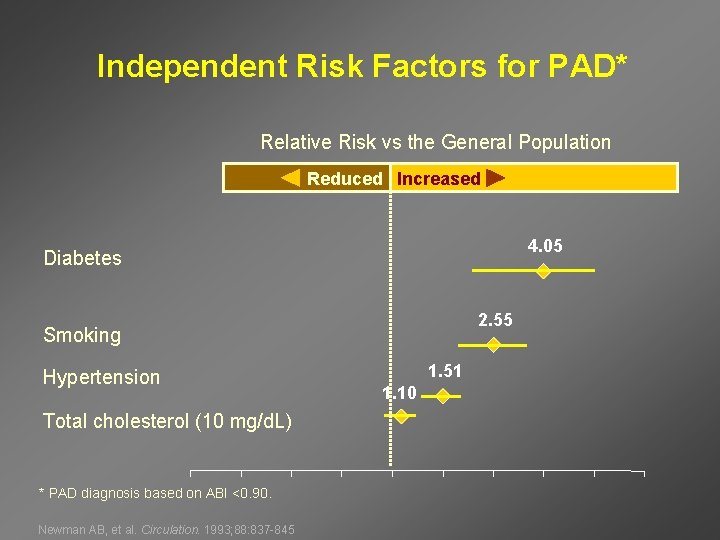

Independent Risk Factors for PAD* Relative Risk vs the General Population Reduced Increased 4. 05 Diabetes 2. 55 Smoking Hypertension Total cholesterol (10 mg/d. L) * PAD diagnosis based on ABI <0. 90. Newman AB, et al. Circulation. 1993; 88: 837 -845 1. 51 1. 10